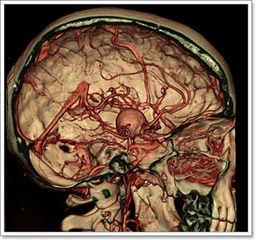

Kireçlenmenin TeşhisiKireçlenme teşhisi genellikle fiziksel muayene ve görüntüleme yöntemleriyle konur. Doktor, hastanın semptomlarını değerlendirir ve eklem hareketliliğini test eder. Ayrıca, röntgen veya manyetik rezonans görüntüleme (MRG) gibi yöntemler kullanarak eklemlerdeki değişiklikleri gözlemleyebilir. Kireçlenme Tedavi YöntemleriKireçlenme tedavisi, hastalığın şiddetine ve bireyin genel sağlık durumuna bağlı olarak değişiklik gösterebilir. Tedavi yöntemleri arasında: